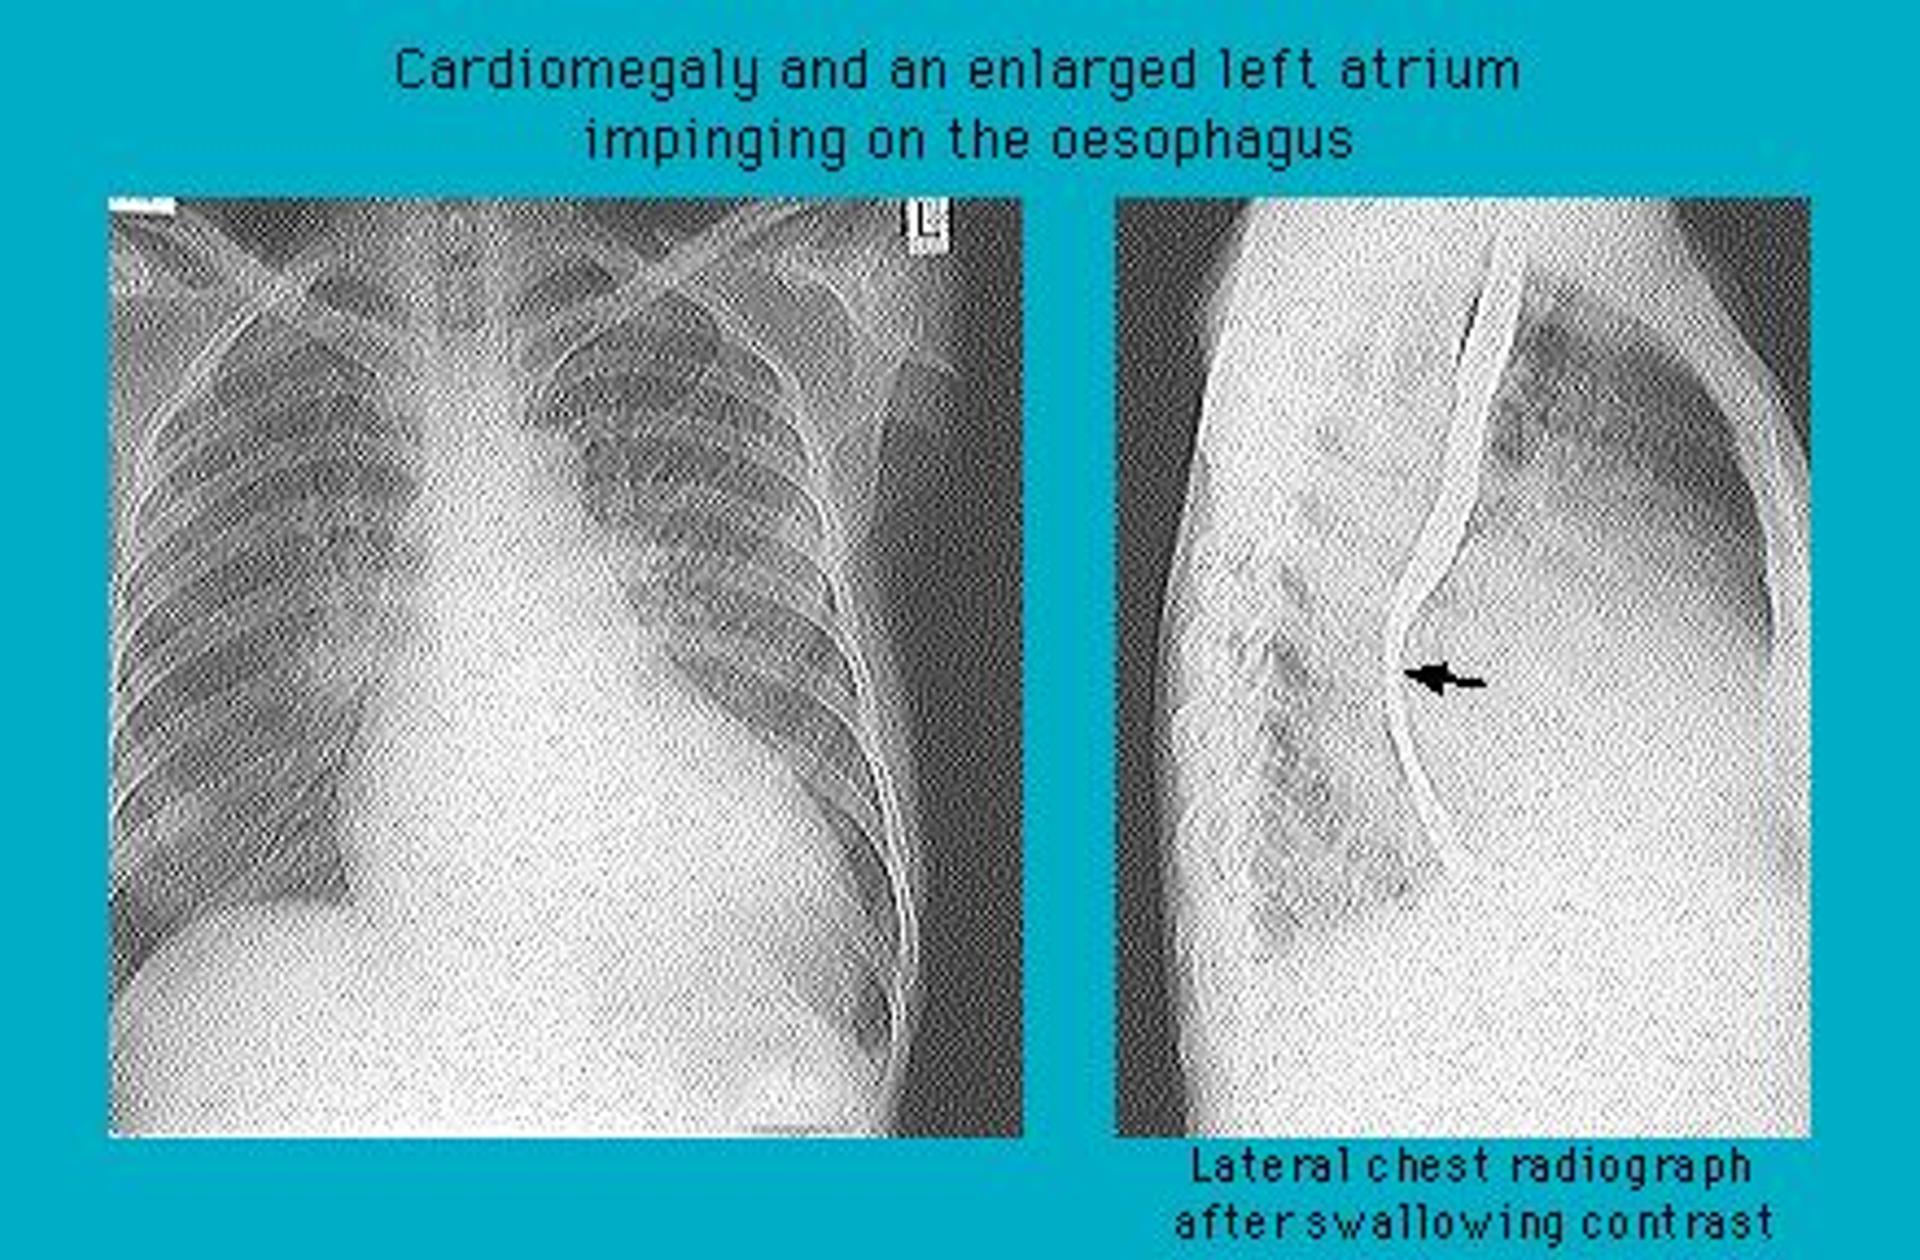

Contrast radiograph showing enlarged left atrium